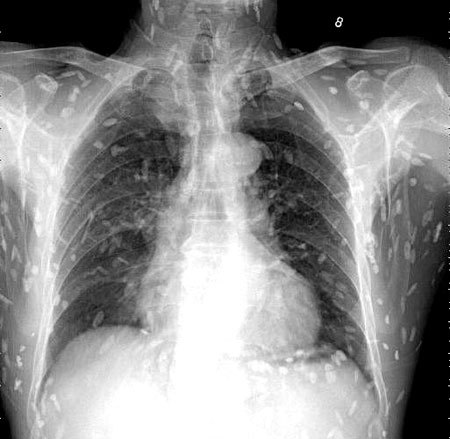

엑스레이를 찍어보니, 온몸에 촌충 같은 기생충이 퍼져있는 것이 Xray사진에 찍혔다.

기침으로 인한 고통을 호소한 환자를 진료하던 의료진은 환자의 엑스레이 사진을 보고 경악했습니다. 엑스레이 촬영물에는 여러 마리의 촌충과 유충이 가득 찍혀있는 것이었습니다.

브라질의 한 의료진이 소셜네트워크서비스(SNS)에 기생충에 감염된 엑스레이 사진을 공개했습니다. 사진에는 몸속에 있는 기생충이 죽어 석회화된 수백 개의 점 형상이 보였습니다.

특히 유충이 근육이나 뇌 조직에 침투한 모습은 매우 충격적이었습니다. 이러한 증상은 유구조충의 유충에 의한 인체감염증으로, 유구 낭미충증이라고도 불립니다.